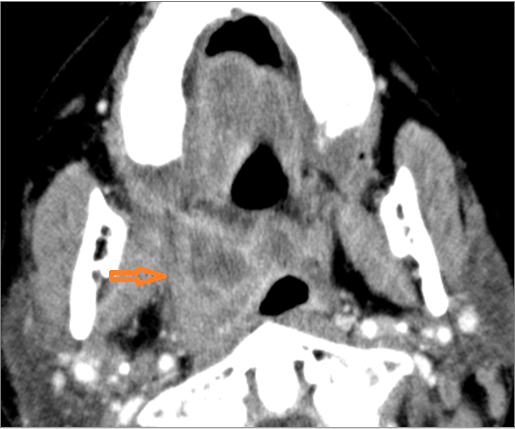

There is excessive enhancement or thickening of the mucosa or hypertrophy of the palatine or lingual tonsillar tissue or the lymphoid tissue along the glossotonsillar sulci and posterior pharyngeal wall.

There is abscess at the periphery of the lymphoid tissue of the palatine tonsil within the potential peritonsillar space.